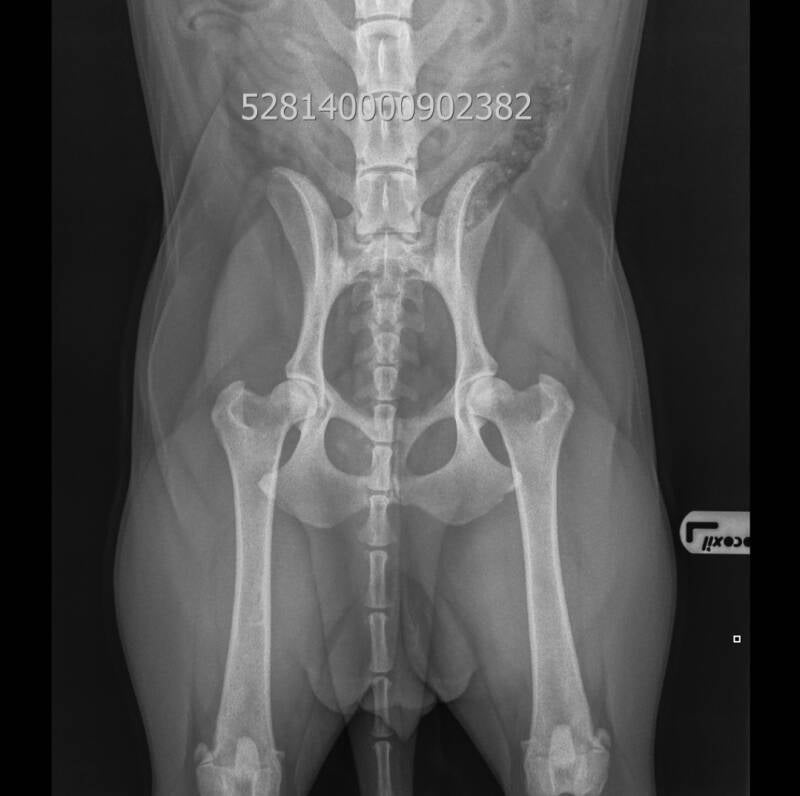

Hieronder treft u eerst een korte uitleg aan gevolgd door de uitslag aan van het formele HD onderzoek van Resa. Daaronder kunt u zelf de genomen heupfoto bekijken. Klik voor een uitleg over de uitslag op: Toelichting uitslag onderzoek

Uit onderstaande uitslag blijkt voor Yazz:

• HD A (=negatief):                                                                    Op basis van de röntgenfoto vrij van HD

Foto genomen: Dierenarts mevrouw M. van Ekeris

Foto datum: 03 september 2025